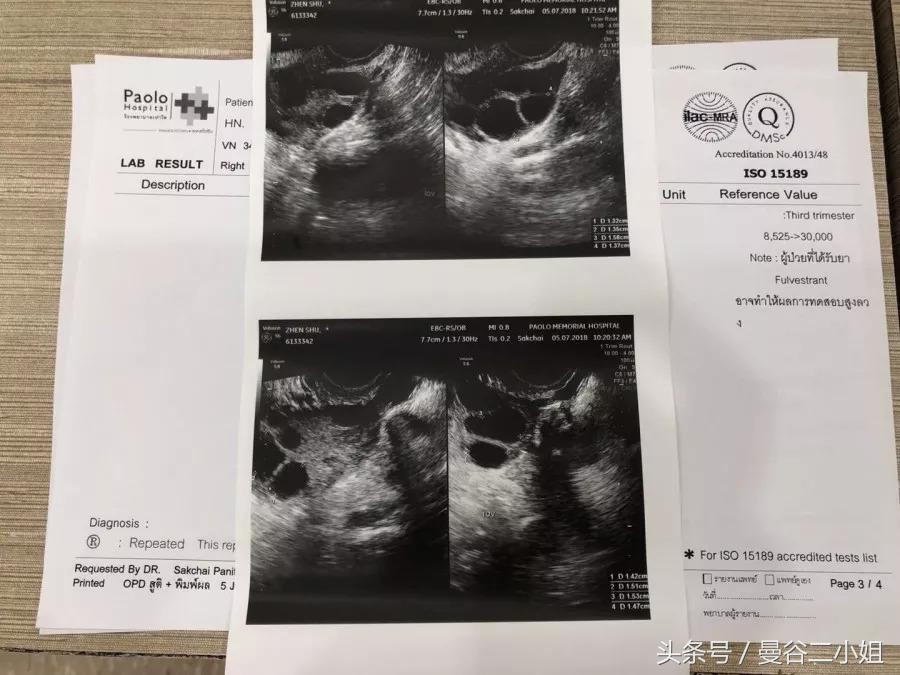

27号这天,经期一到立马就去医院验血,做阴道B超,看激素水平和卵泡数量。我左边6颗,右边10颗,情况非常好。

又一轮验血、量血压,测体重做B超。可以看到左边卵巢已经发育起来6颗卵子,而右边只有7颗,还有3颗没有发育起来。

今天检查的结果很棒!各项指标正常,上次没有促排起来的3个卵子也成熟了。